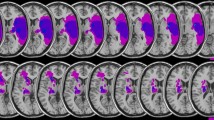

Cerebellar stroke lesion location and distribution were assessed based on MRI and CT images acquired for clinical purposes during the acute phase of the cerebellar stroke. Individual FLAIR-weighted images were normalized to Montreal Neurological Institute (MNI) space in SPM 12 (https://www.fil.ion.ucl.ac.uk/spm/software/). Anatomical labelling of damage to specific cerebellar structures was based on automated anatomical labelling [34] distributed with MRIcron (https://www.nitrc.org/projects/mricron) and the SUIT atlas [35, 36].

Demographic baseline characteristics (Table 1) were similar in healthy controls and cerebellar stroke patients except for a slightly higher BDI score in the patient group. However, mean BDI scores in patients were, similar to healthy controls, below the cut-off for even a mild depressive syndrome. Detailed information on lesion characteristics in the cerebellar stroke patients is given in Table 2 and Fig. 2. Out of 23 cerebellar stroke patients, 18 had suffered from unilateral cerebellar stroke (7 in the left and 11 in the right cerebellar hemisphere) and 5 patients had suffered from bilateral cerebellar stroke.

Visualization of lesion distribution. Colorbar specifies number of patients (n = 23) with overlapping lesions in each voxel. Hot colors indicate a greater number of patients with lesions in the respective region. Maximum lesion overlap (n = 12) was found in the right postero-lateral cerebellum corresonding to Crus II (MNI coordinates 20, − 69, − 40). For this representation, individual FLAIR-weighted images were normalized to Montreal Neurological Institute (MNI) space in SPM 12 (https://www.fil.ion.ucl.ac.uk/spm/software/). Lesions were manually delineated and superimposed on the SUIT template using MRIcron (https://www.nitrc.org/projects/mricron). RH, right cerebellar hemisphere; LH, left cerebellar hemisphere